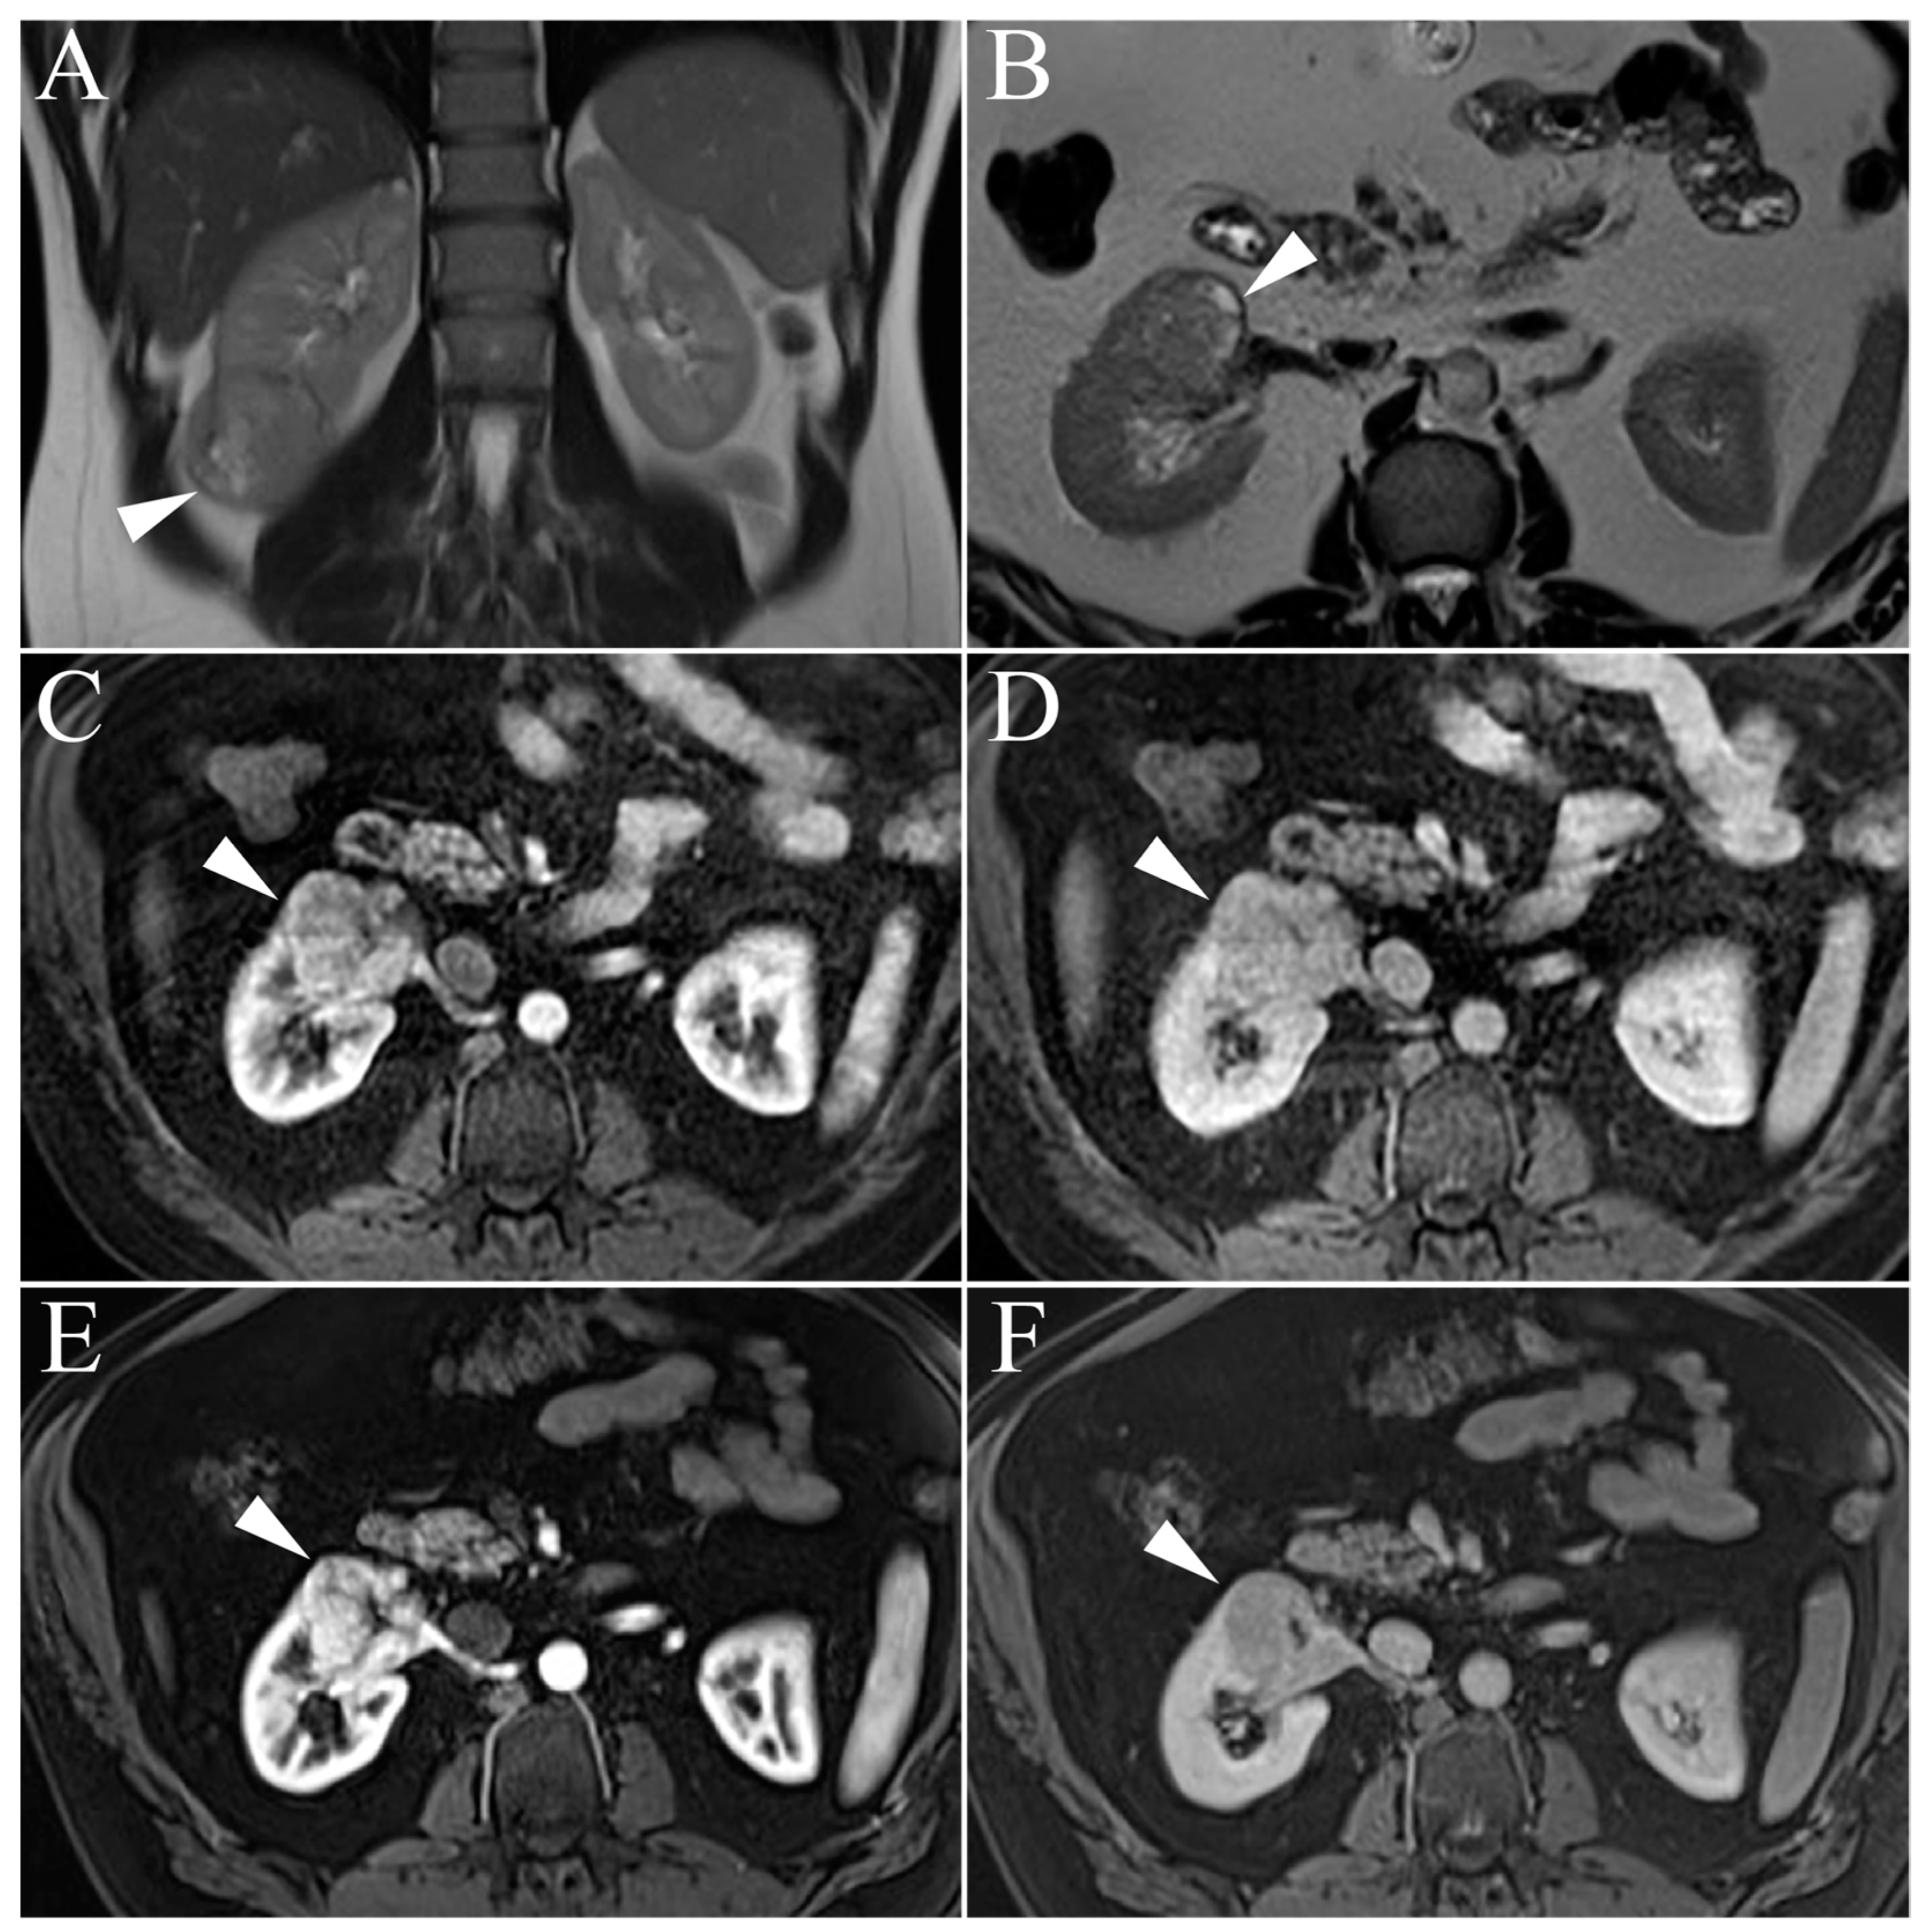

5.1. Clear Cell Renal Cell Carcinoma

| Clear Cell RCC | Heterogenous, high T2-intensity Avid enhancement in corticomedullary and nephrogenic phases Microscopic fat as see on dual echo T1W in- and out-of-phase Invasion into surrounding vessels (esp. renal vein or IVC) Presence of necrosis or intralesional calcification |